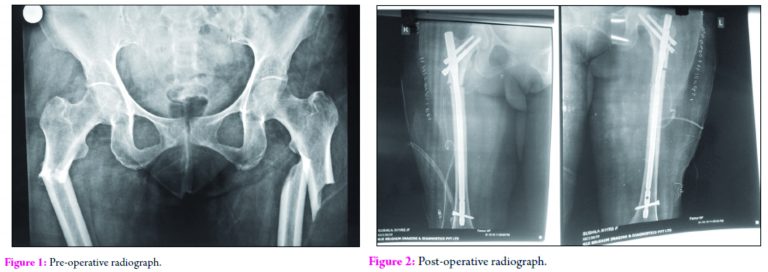

Case Presentation: A postmenopausal female of Rheumatoid Arthritis aged 56 years, presented to our emergency department with history of trivial fall at home. Following the fall, she was unable to bear weight on bilateral feet and complained of deformity. Past history revealed consumption of bisphosphonates (Tab. Alendronate 10mg) for the past 4 years and glucocorticoids for Rheumatiod arthritis. Radiographs were taken, which revealed bilateral pathological subtrochanteric fracture femurii. Aafter obtaining necessary fitness, the patient was taken up for surgery. Closed Reduction and Internal fixation with Long Proximal Femoral Nail was done. Bisphosphonate intake was stopped and teriparatide 20 microgram/day subcutaneously given for 3 months. Fracture healed after 3 months and patient resumed her daily activities

A postmenopausal female of Rheumatoid Arthritis aged 56 years, presented to our emergency department with history of trivial fall at home. Following the fall, she was unable to bear weight on bilateral feet and complained of deformity. Past history revealed consumption of bisphosphonates (Tab. Alendronate 10mg) for the past 4 years and glucocorticoids for Rheumatiod arthritis. Radiographs were taken, which revealed bilateral pathological subtrochanteric fracture femurii. Aafter obtaining necessary fitness, the patient was taken up for surgery. Closed Reduction and Internal fixation with Long Proximal Femoral Nail was done. Bisphosphonate intake was stopped and teriparatide 20 microgram/day subcutaneously given for 3 months. Fracture healed after 3 months and patient resumed her daily activities